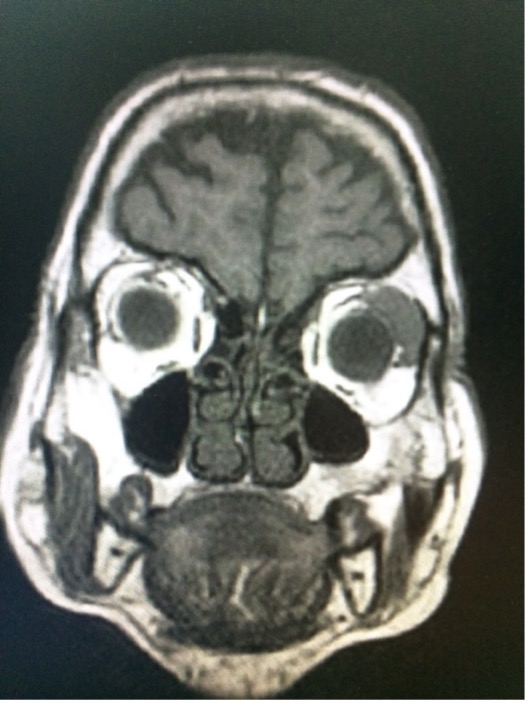

- Resonancia Magnética

Las nuevas tecnologías permiten obtener imágenes muy precisas que nos ayudan en el diagnóstico del tumor y nos guían durante la cirugía.